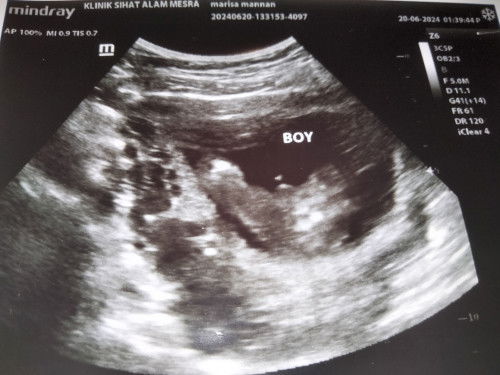

very excited to become a mother

Tumpang tnya klau nmpak bgini confirm boy kah

#bantujawab